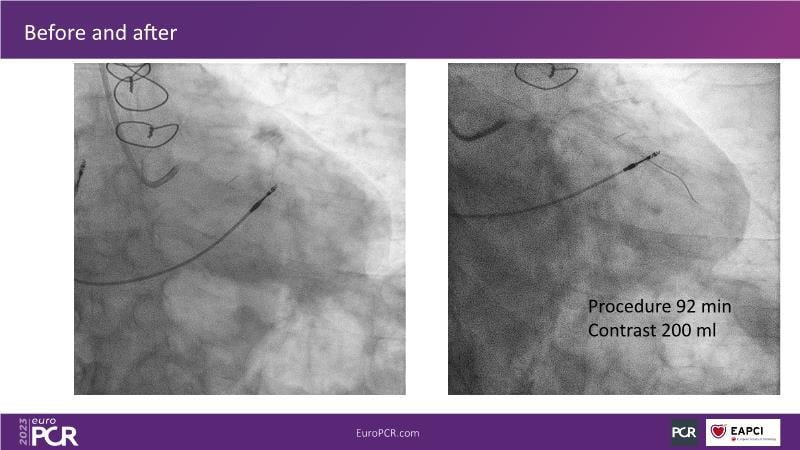

The aim of this session is to address the question of how to optimise outcomes for high-risk patients by analyzing two real-life cases for discussion: a distal calcified left main trifurcation and a high-risk PCI with orbital atherectomy.